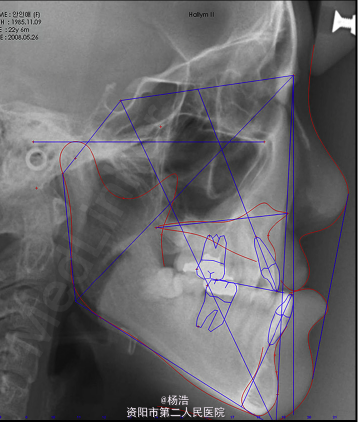

面中份凹陷,下颌体长度过长,面下1/3过长。口内:安氏III类磨牙关系,前牙反合,上颌右偏,上颌第二前磨牙缺失,14牙腭侧异位,上中线右偏3mm,锥形侧切牙 全景示:原始腭裂在上颌左侧侧切牙处。 侧位片显示骨性III类,上颌后缩,离散生长型。

诊断:唇腭裂术后,骨性III类,前牙反合 治疗目标:解决面中份凹陷和上颌的偏斜,增加面部美观,调整咬合关系。 处理:先对狭窄的上颌骨进行牵张成骨,见下图所示制作装置,牵张成骨后上固定矫治器进行正合手术前正畸治疗,拔除14牙,排齐整平上下牙列,去除代偿;正合手术行LeFort I型截骨术前移上颌5mm,及BSSRO后退下颌6mm,颏成形术以减少面下部垂直高度。术后8个月精细调整,结束治疗。 上下前牙舌侧丝固定保持。 治疗后两年复查,效果依然稳定,患者满意。

讨论:此病例为什么要先牵张成骨?有研究表明上颌LeFort I截骨前移术不稳定有复发的趋势,且这种趋势随着前移量的增大而增大,此病例上下颌骨差距很大,直接截骨前移的量非常大,手术风险大且术后效果不稳定,所以先牵张成骨,测量牵张成骨后的侧位片显示上颌前移了7mm,大大减少了手术的难度。